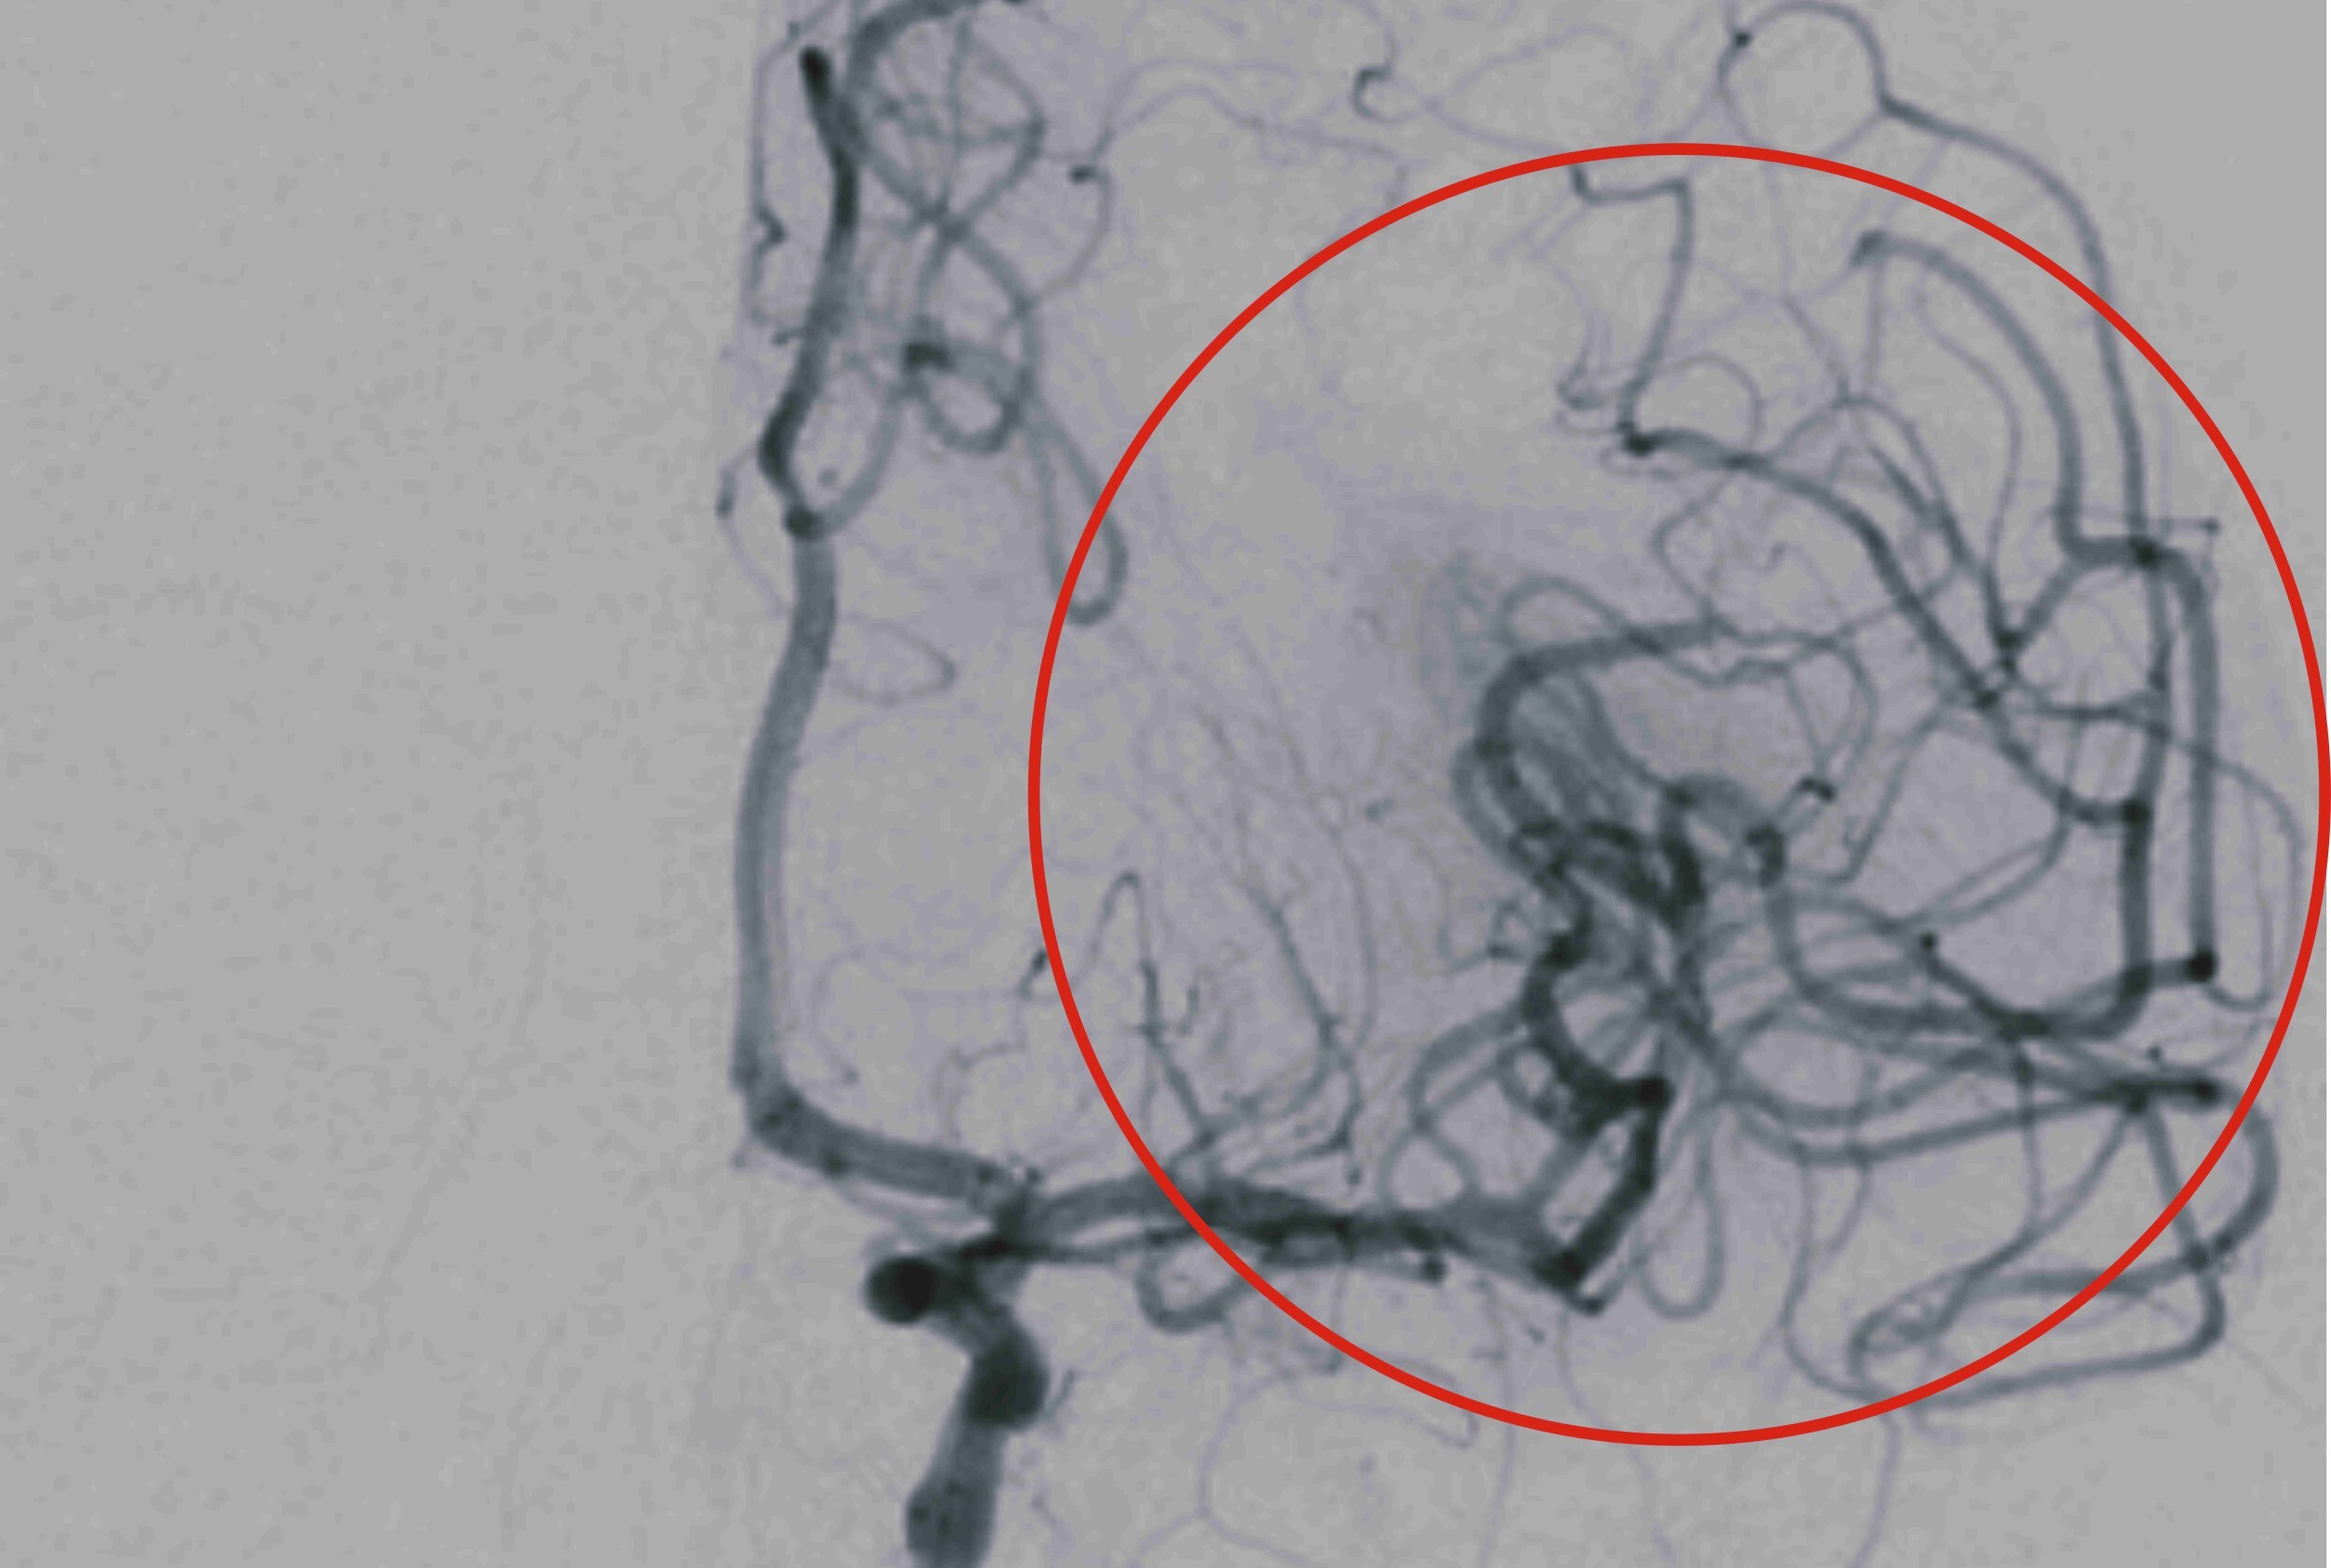

▲ 小惠(化名)接受取栓治療後,阻塞的血管幾乎完全打通。(圖/彰基提供)

彰基影像醫學部張梓恩醫師透露,小惠的中風是由於左側中大腦動脈的完全阻塞所引起的,經過動脈取栓手術後,阻塞的血管幾乎完全打通,使得腦部灌流得以恢復,進而降低腦細胞的損傷並有助於功能的恢復。張醫師也提醒,近年來中風的發病年齡有明顯年輕化,尤其是與不良生活習慣有關的因素,應更加重注意與控制。